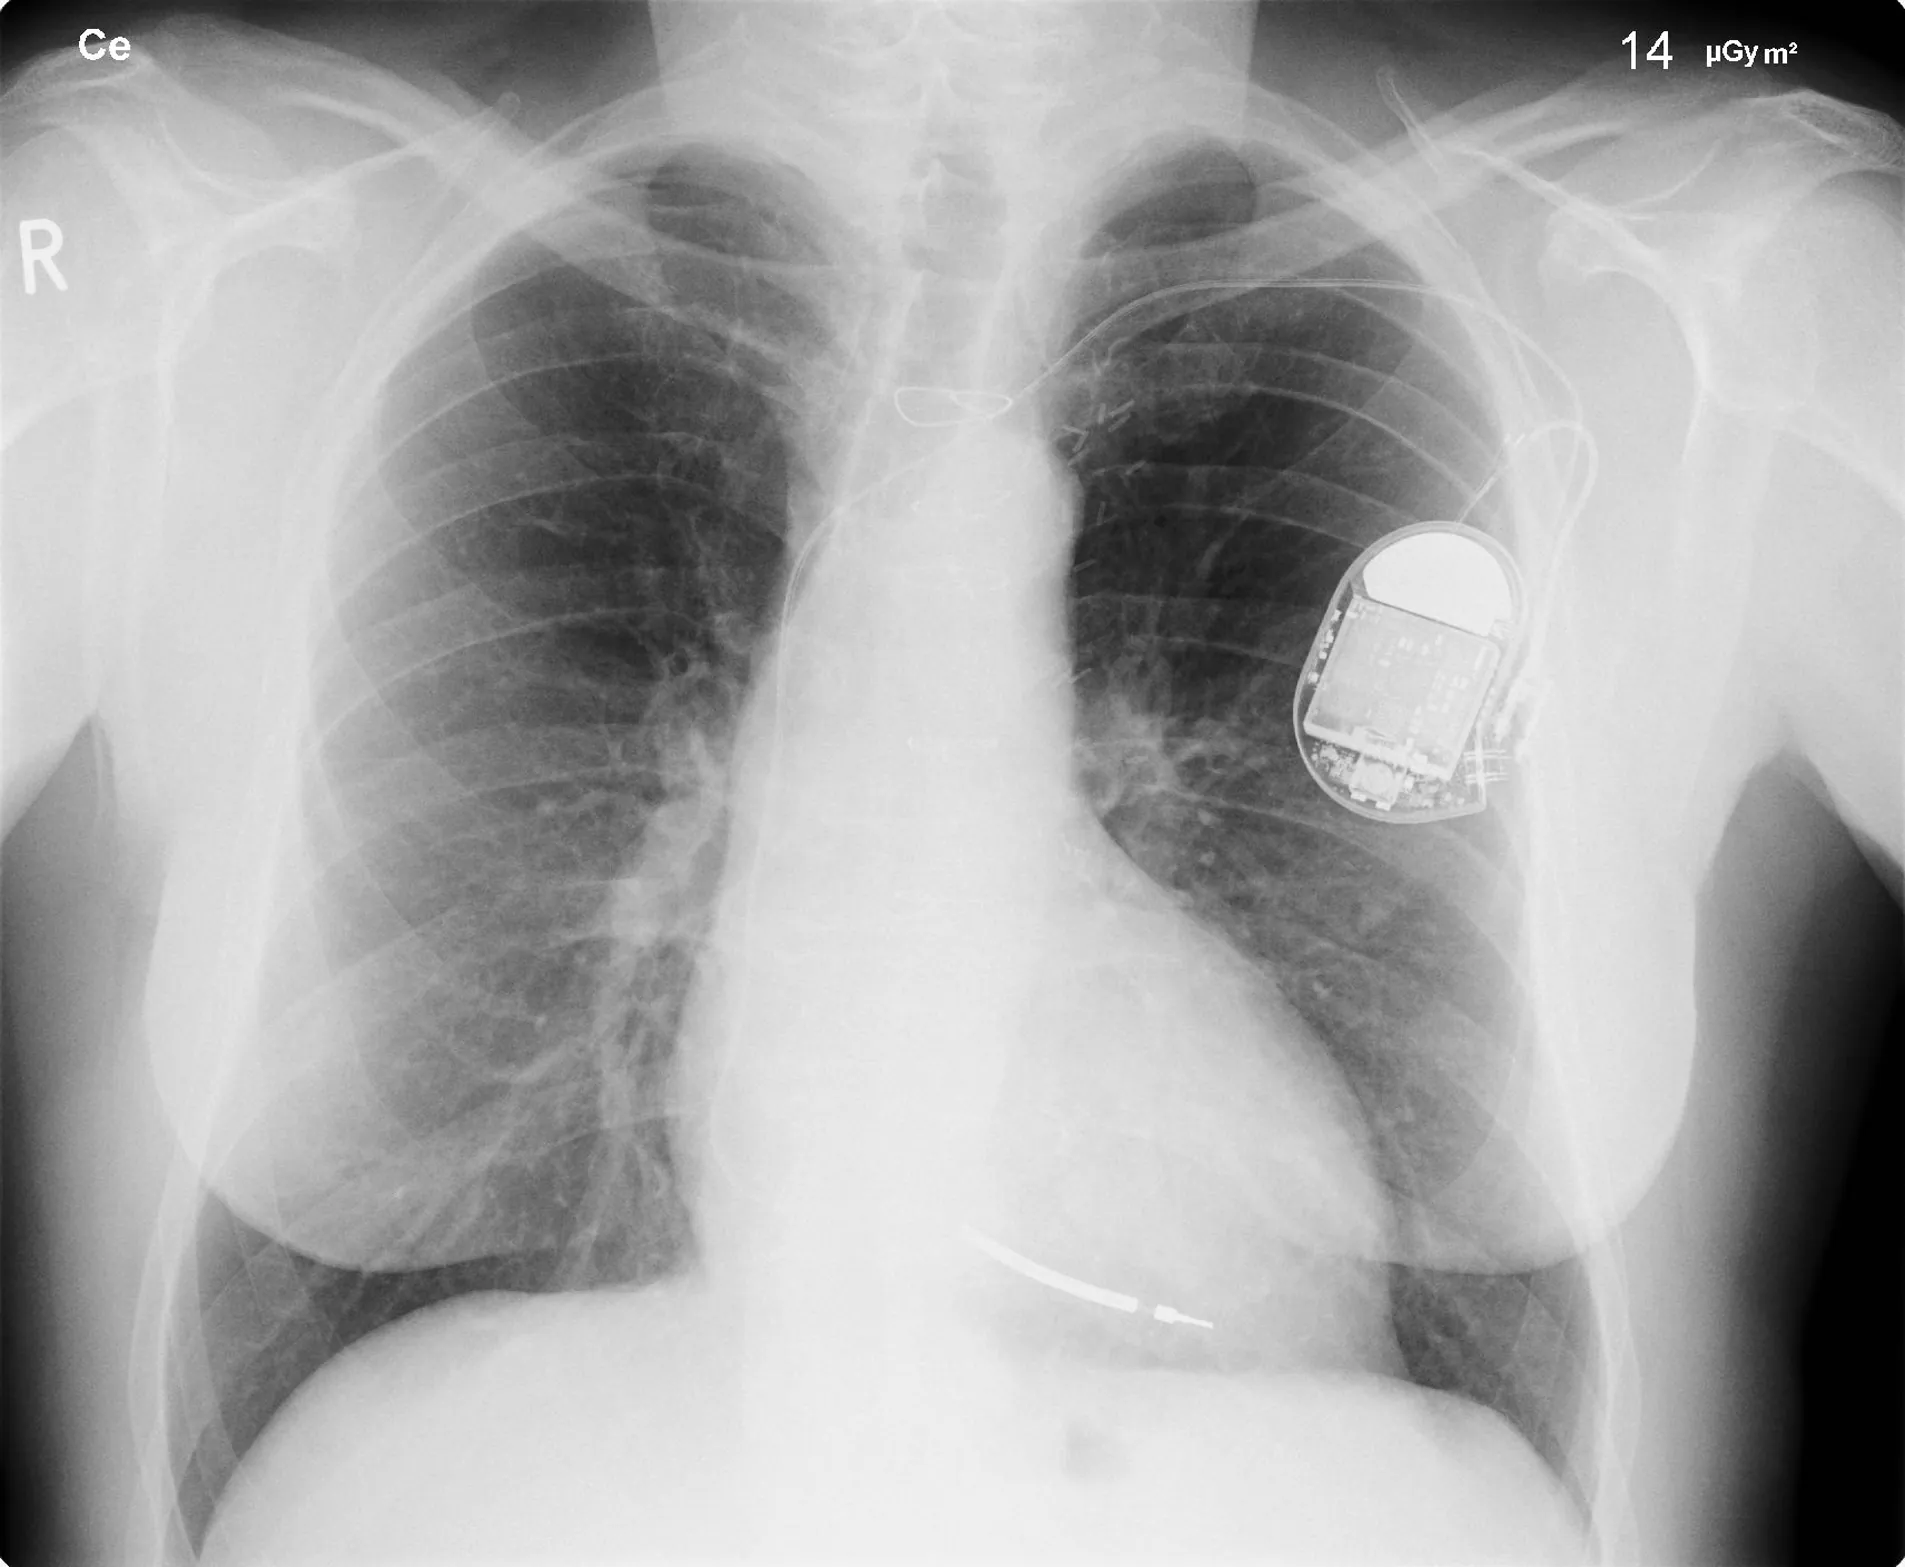

An X-ray image of a person’s chest is shown, clearly showing a pacemaker in the left side.

Figure 30.25 This x-ray image of a person’s chest shows many details, including an artificial pacemaker. (credit: Sunzi99, Wikimedia Commons)

The most common x-ray images are simple shadows. Since x-ray photons have high energies, they penetrate materials that are opaque to visible light. The more energy an x-ray photon has, the more material it will penetrate. So an x-ray tube may be operated at 50.0 kV for a chest x ray, whereas it may need to be operated at 100 kV to examine a broken leg in a cast. The depth of penetration is related to the density of the material as well as to the energy of the photon. The denser the material, the fewer x-ray photons get through and the darker the shadow. Thus x rays excel at detecting breaks in bones and in imaging other physiological structures, such as some tumors, that differ in density from surrounding material. Because of their high photon energy, x rays produce significant ionization in materials and damage cells in biological organisms. Modern uses minimize exposure to the patient and eliminate exposure to others. Biological effects of x rays will be explored in the next chapter along with other types of ionizing radiation such as those produced by nuclei.